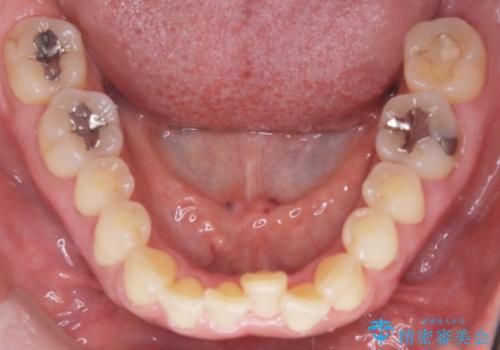

- 前歯の軽度なガタつき(叢生)を気にされてご来院されました。精密な検査の結果、抜歯は不要で、わずかなスペースを確保することで歯並びを整えられると診断。患者様のご希望と状態に合わせ、目立ちにくい審美ブラケットを使用したワイヤー矯正による治療計画を立案しました。スペース確保は、奥歯を少し後ろへ動かす遠心移動と、歯の側面をわずかに削る**IPR(歯間乳頭保護下ストリッピング)**を併用し、約1年間での治療完了を目指しました。

今回の矯正治療では、歯の色に近い目立たない審美ブラケットとワイヤーを使用しました。

スペース確保のために、まず奥歯全体をわずかに後方へ動かす遠心移動を実施し、前歯を並べるためのスペースを確保。さらに、安全性に配慮しながら歯の側面をわずかに削るIPRを併用し、デコボコを解消しました。

ワイヤー矯正ならではの確実な歯のコントロールにより、当初の計画通り約1年という短い期間で、前歯のガタつきが解消。見た目が美しく整っただけでなく、清掃しやすい機能的な歯並びを獲得していただけました。